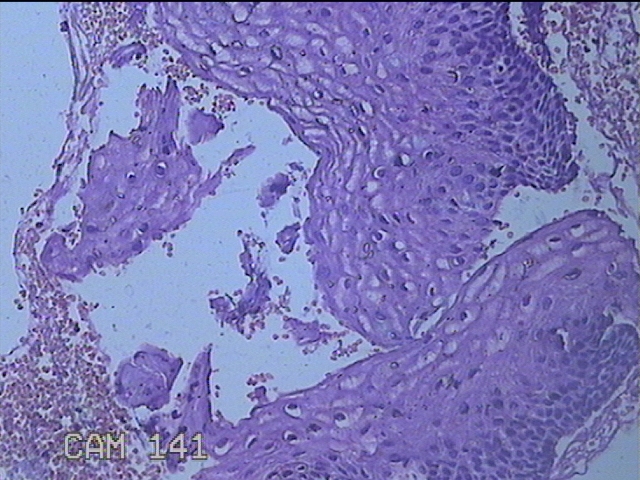

宫颈6点组织

性别

女

年龄

48岁

临床诊断

人乳头瘤病毒感染;慢性子宫颈炎

一般病史

发现高危HPV58及68阳性。

标本名称

大体所见

灰白粉红色红色组织1.3x0.3x0.2cm一块。

鳞状上皮低度病变。